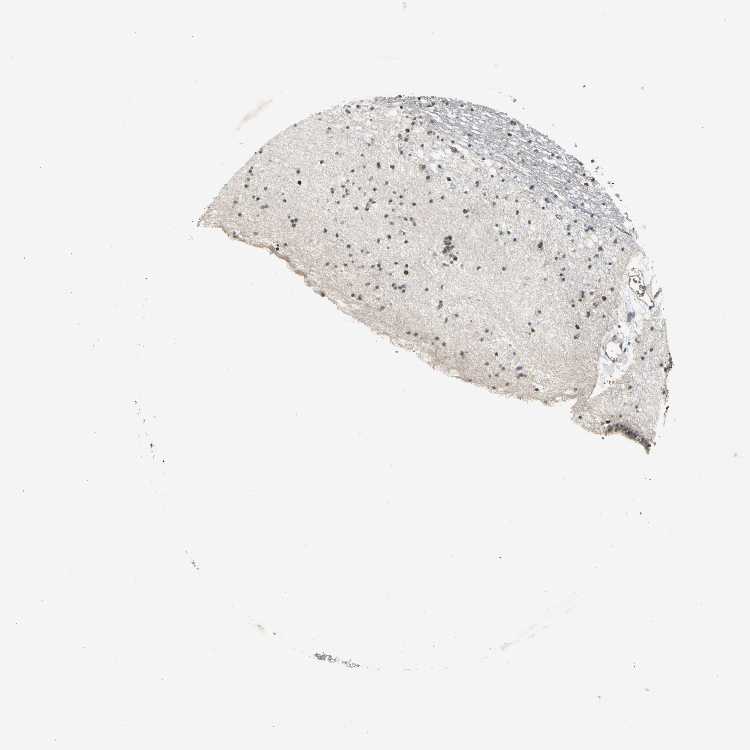

CAUDATE - Antibody stainingi

Antibody staining in the annotated cell types in the current human tissue is reported as not detected, low, medium, or high, based on conventional immunohistochemistry profiling in selected tissues. This score is based on the combination of the staining intensity and fraction of stained cells.

Each image is clickable and will lead to virtual microscopy that enables deeper exploration of all samples and also displays staining intensity scores, fraction scores and subcellular localization as well as patient and tissue information for each sample.

Antibody HPA029722Antibody HPA029723Antibody CAB005072

Glial cells LowLowMedium

Neuronal cells MediumNot detected-